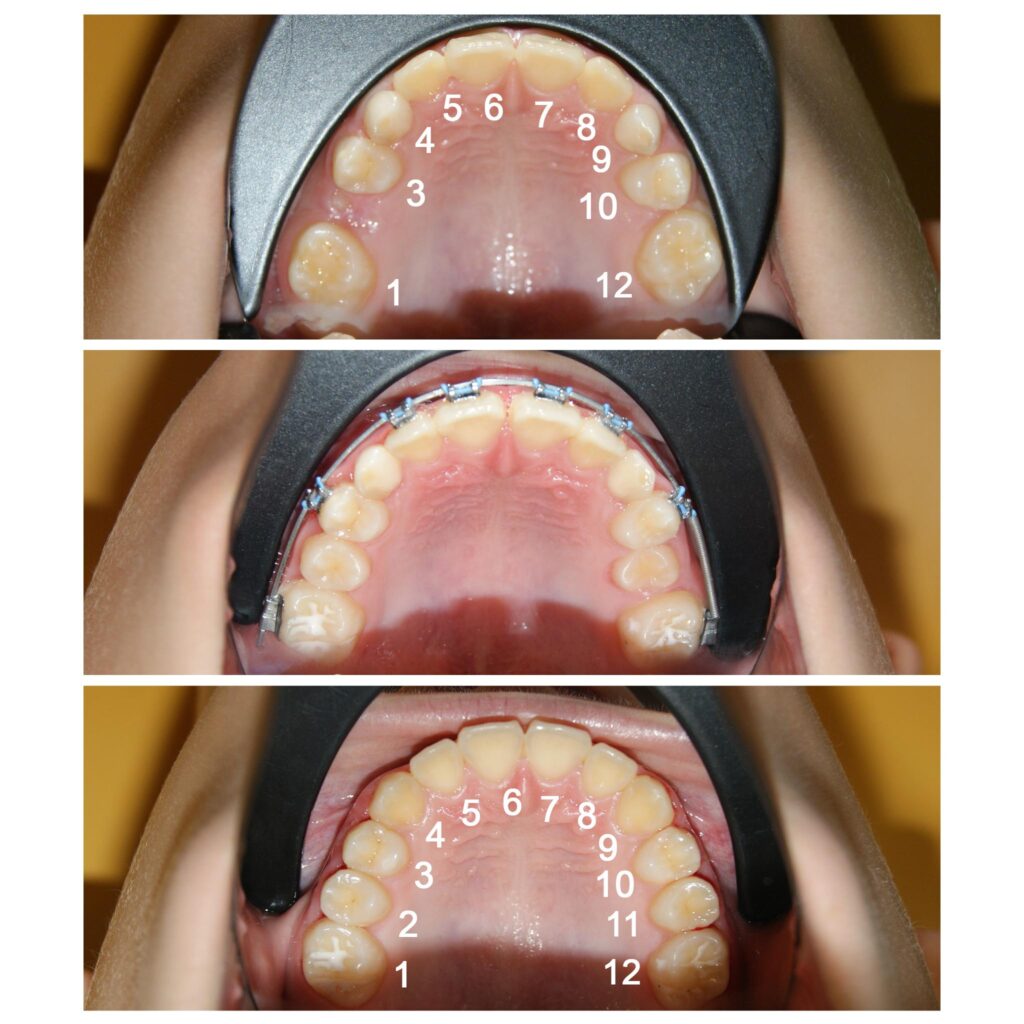

Redeschiderea spațiilor pentru caninii definitivi (a se observa că pe o parte spațiul era închis complet)

Recâștigarea spațiilor pierdute pentru dinții numerotați cu 2 si 11. Dacă nu am fi pus aparatul ortodontic fix dinții ar fi rămas blocați în intriorul osului, cu consecințe dramatice